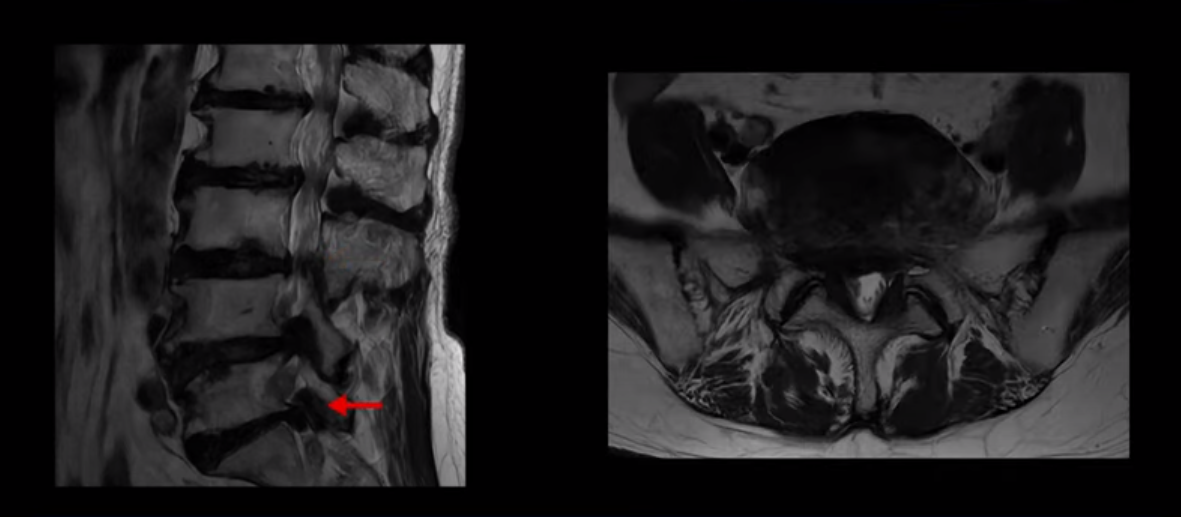

이 환자분은 MRI로 보면 허리 여러 마디가 신경이 매우 심하게 눌려 보이는 분입니다. 이분 MRI를 보면서 간단히 설명해 드린 후 어떻게 이렇게 신경이 심하게 눌린 환자분이 수술 없이 근육신경재활치료로 좋아질 수 있는지, 다리가 아파 걷지 못하는 환자가 어떻게 안 아프고 잘 걸을 수 있게 되는지, 10년 동안 괴로웠던 양 발의 시린 증상은 어떻게 사라질 수 있는지, 치료는 어떻게 하는지 자세히 설명 드리겠습니다.

MRI 보시면 (2-8) 허리의 5마디가 전부 다 심하게 퇴행되어 있습니다.

5마디 전부 다 심한 중심성 협착이 있습니다.

이렇게 모두 다 심하게 막히는 경우는 드문데요. 또한 오른쪽, 왼쪽 신경이 빠져나가는 추간공도 다 심하게 막혀있습니다.

오른쪽, 왼쪽 이렇게 신경 구멍들이 다 좁아지고 신경이 눌리니까 양쪽 다리가 발바닥까지 아파서 걷기 어렵고 양쪽 발이 10년 넘게 시린 겁니다. 당연히 수술해서 눌린 신경을 풀어줘야 한다고 들으셨는데요. 이런 환자분을 어떻게 수술 없이 치료할까요? 지금부터 설명해 드립니다.

이분 신경이 눌리는 증상은 오래됐지만, 증상이 아주 심해진 건 올해 들어와서입니다. 그럼, 이분 MRI 영상도 이렇게 심하게 안 좋아진 게 올해 들어와서일까요? 이분의 MRI로 보이는 협착은 아주 오래된 겁니다. 그래서 신경 구멍이 심하게 좁아진 것도 올해가 아니고 오래된 겁니다. 작년, 재작년에 훨씬 덜 아팠을 때 MRI를 찍었어도 신경 구멍 좁은 정도는 별반 차이가 없었을 겁니다.